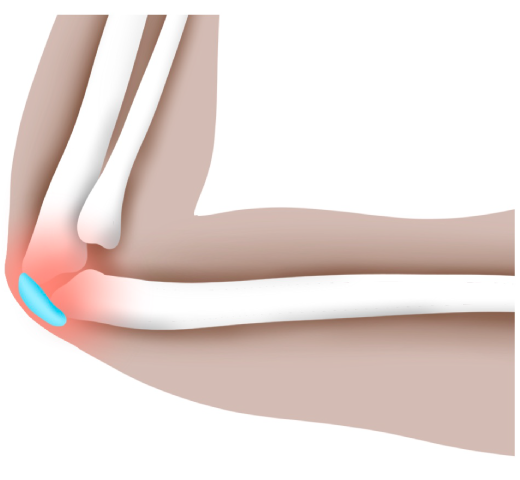

팔꿈치 부위 척골의 끝과 표피사이에 위치한 일종의 쿠션 같은 조직인 점액낭에 생기는 염증성 질환입니다. 팔꿈치를 책상에 장시간 반복적으로 기대는 습관이 있을 경우 만성염증으로 발생할 수 있고, 외상이나 낙상으로 직접적 타격에 의해 손상을 입은 경우 급성 염증으로 나타날 수 있습니다.

□ 팔꿈치 뒷 부분에 물혹이 있는 듯한 말랑말랑한 느낌

□ 어딘가에 팔꿈치가 닿을 때마다 통증이 발생

□ 팔을 90도 이상 구부릴 경우 통증 발생